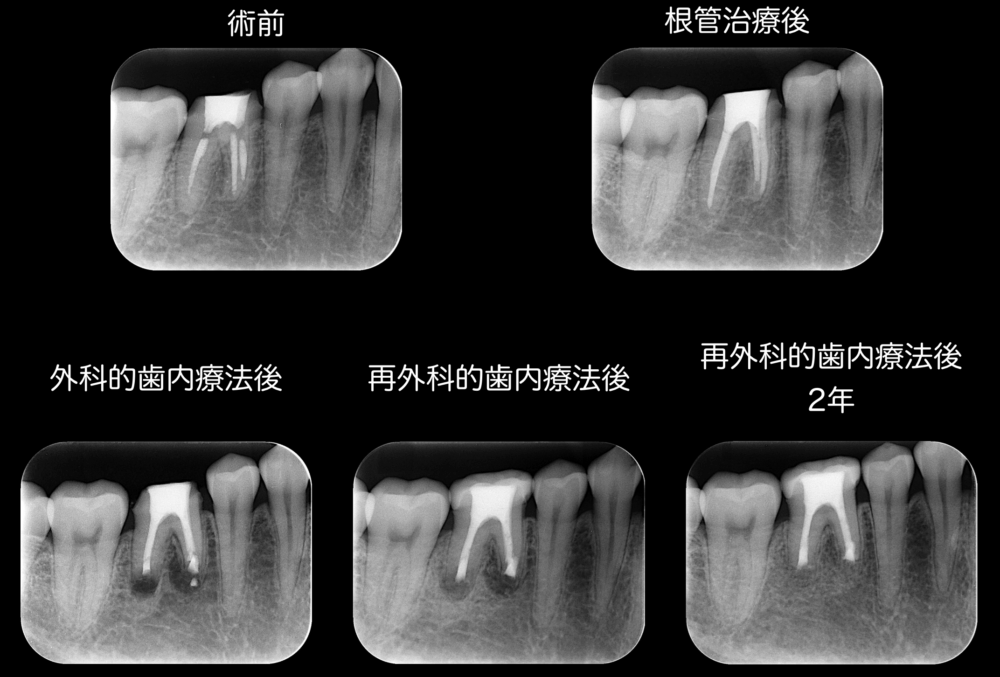

症例2:基本コンセプトを遵守している根管治療と外科的歯内療法で痛みが取れたケース

根管治療中から継続した痛みがあり、薬を詰めてはいる(根管充填)けれど、痛みが依然として残っていて外科的歯内療法で痛みが改善した症例です。

痛みの原因は、根の先の細菌を除去しきれなかったからではないか、と考えています。

根の先の部分は少しカーブしている状態で、このカーブの部分に器具を到達させることが難しく、機械的拡大ができず、細菌を除去できなかったから、痛みが残ってしまった、と考察しています。

本症例は根尖部透過像を認めませんでしたが、患者さんは痛みを訴えていました。おそらく、根尖にレッジが形成されたため未形成部分ができ、痛みを発していたのではないかと考えています。実は、根管治療後外科的歯内療法を行って一度は痛みが改善されたものの、外科的歯内療法後1年ほど経過した際に、患者さんは痛みが再発した、とおっしゃっていたことがあり、以前と同様に根尖部透過像を認めてはいませんでしたが、再外科を行いました。再外科後2年が最長の観察期間時点において、痛みの再発はなく経過良好です。